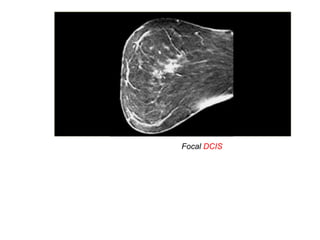

Clumped enhancement is the most important non-mass enhancing

pattern to recognize.

It has a 60% chance of cancer (typically DCIS).

On the left two examples of clumped enhancement in DCIS

Focal DCIS